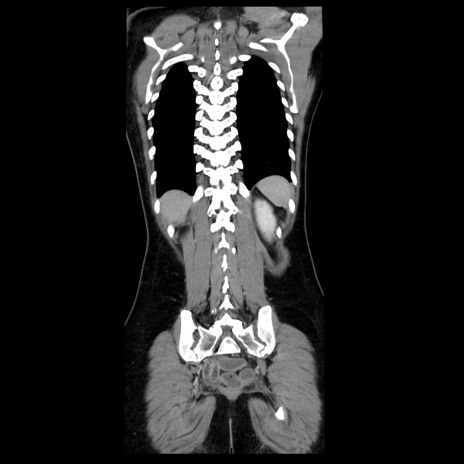

症例39(冠状断像)

【症例】40歳代女性

【主訴】上下腹部痛

【現病歴】2日目から下腹部痛あり。夜間は痛みで眠れなかった。昨日より上腹部痛と下痢が出現。臥位で痛みは軽快したため、休んでいた。本日になって臥位でも立位でも痛みが強くなってきたため救急要請。

【既往歴】子宮内膜症

【身体所見】部:平坦・軟、左上下腹部に圧痛あり、反跳痛あり。

【データ】WBC 21800、CRP 26.78

CT